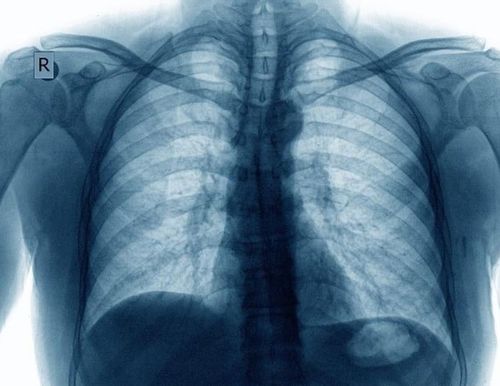

正常胸透

胸透正常图片